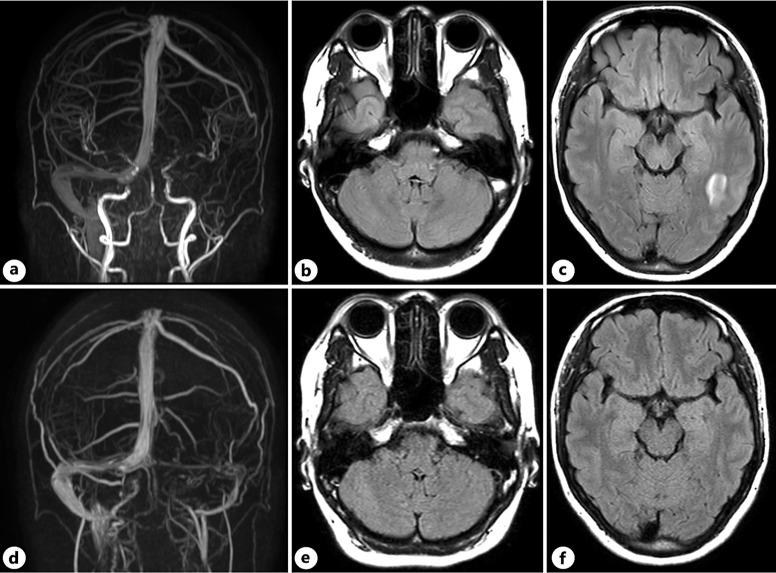

一名29岁的尼泊尔女性在首次妊娠期间发生DVT。检查未发现血栓形成倾向。血栓通过口服抗凝药物得以溶解,3个月后停药。在第二次妊娠期间,开始预防性皮下注射肝素以预防静脉栓塞。在停止使用肝素几天后,她出现左枕部疼痛,磁共振静脉造影显示左CVST。开始口服抗凝药物治疗,她的头痛在数天内缓解。进一步的血液检查显示Lp(a)水平异常升高,达113mg/dL。6个月后,CVST部分再通。